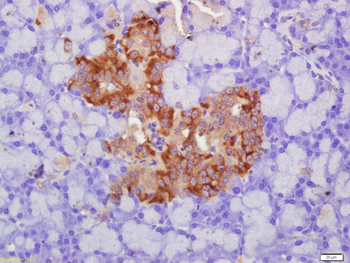

GLUT2 Rabbit Polyclonal Antibody

FC, IF, IHC-Fr, IHC-P, WB

应用稀释比例:WB=1:500-2000, IHC-P=1:100-500, IHC-F=1:100-500, IF=1:100-500, Flow-Cyt=1μg /test